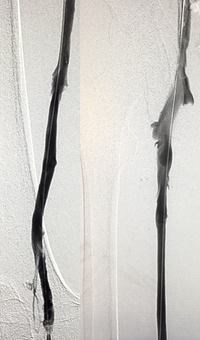

Xray of Iliofemoral thrombus pre-treatment and Power Pulse™ delivery

Iliofemoral thrombus pre-treatment (left) and Power Pulse delivery (right)

Xray of veins post-ZelanteDVT mechanical thrombectomy.

Post-ZelanteDVT  Mechanical Thrombectomy

Xray of veins post-ZelanteDVT runtime 415 seconds.

Post-ZelanteDVT runtime 415 seconds

Images Courtesy of Charles Wyble M.D. – Vascular Surgical Associates, Marietta, Georgia – January 5, 2016